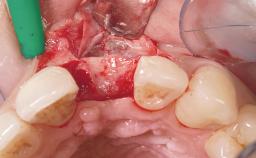

A 42-year-old female patient was referred to our clinic at the School of Dentistry of the University of São Paulo in November 2004, presenting a deficient restoration in the upper left central incisor. The clinical examination revealed no gingival retraction or any signs of gingival inflammation and, therefore, previous periodontal treatment was not considered. The patient presented a high lip line at full smile and a thin tissue biotype. This combination characterized a high-risk situation from an anatomic point of view, which required careful preoperative planning and cautious surgical execution.

Abutment Type Customized

Prosthesis Type FDP

Soft Tissue Contour and Volume Ideal